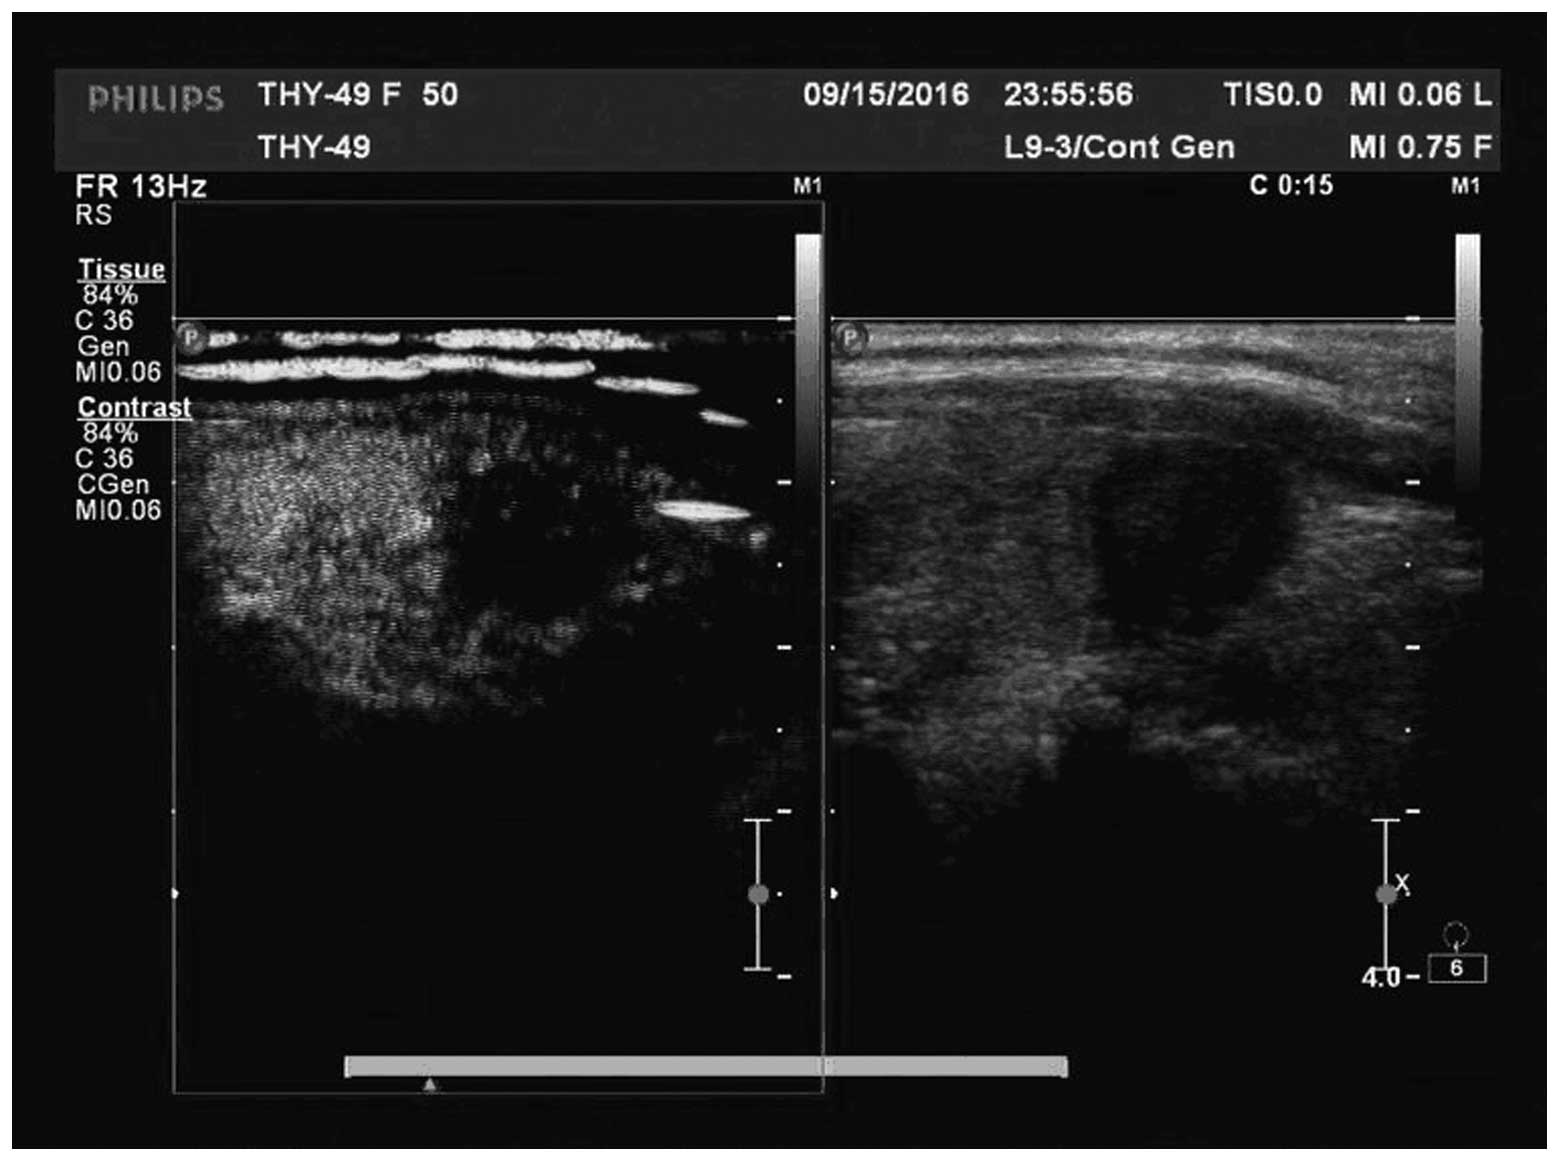

There were three types of manifestation, including irregular weak concentric ring enhancement (Fig. 1), no or weak enhancement (Fig. 2) and uneven enhancement (Fig. 3) in the CEUS images of the 51 nodules in 48 patients. All nodules provided adequate specimens and the satisfaction rate of tissue drawing was 100%. Of the 51 nodules, 44 (86.3%), five (9.8%) and two (3.9%) nodules were pathologically diagnosed as PTC, nodular goiter and focal Hashimoto’s disease, respectively. From the 44 nodules diagnosed as PTC, 43 (97.7%) and 34 (77.3%) nodules were detected by CEUS and conventional ultrasound, respectively, with a significant difference between the two methods (P=0.022). Eleven (25%) nodules were independently detected by CEUS and 31 (70.5%) nodules were detected by CEUS and conventional ultrasound. Only one nodule was not detected (2.3%).

Figure 1

Irregular weak concentric ring enhancement by CEUS (pathologically diagnosed as PTC). CEUS, contrast-enhanced ultrasonography; PTC, papillary thyroid carcinoma.